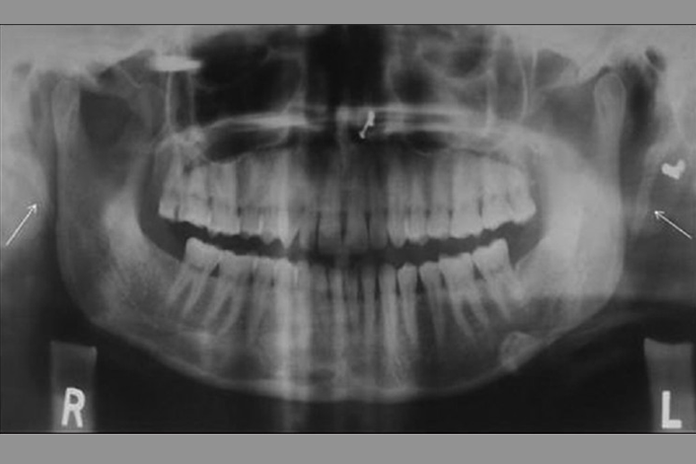

Most symptoms associated with Eagle syndrome are also commonly found symptoms of TMD, making diagnosing Eagle syndrome a little tricky. As a general rule, the dental profession has been taught to evaluate for TMD and treat accordingly. A second review of panoramic images in patients who find little comfort with TMD treatment should be considered. A closer look may reveal an elongation of the styloid process, prompting a referral to an ENT.

However, if your patient has no problematic symptoms and you notice an elongation of the styloid process on panoramic imagery, inform the patient of your finding and advise of the potential for Eagle syndrome symptoms as this discovery in itself does not diagnose the syndrome.

The next time you have a patient complaining of head and neck aches and pains, ask the right questions and obtain a panoramic image. Does their styloid look normal, or is it elongated? TMD pain usually lasts a long time, whereas pain from Eagle syndrome may last only a few seconds upon turning the head.

In summary, Eagle syndrome can mask itself as temporal mandibular disorder, among other things – easily being misdiagnosed and mistreated. Use the guide above to assist with differential diagnosis and expose clear, diagnostic panoramic images. The next time a dental patient complains of TMD-like pain, ask the appropriate questions, review their panorex, and refer as needed.